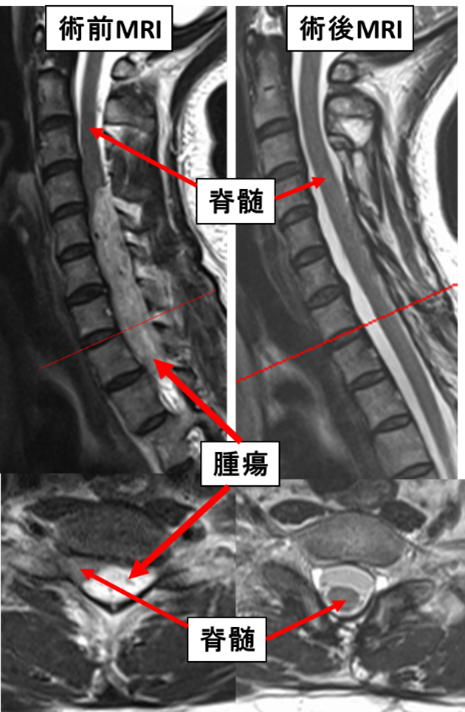

硬膜内髄外腫瘍による重度歩行障害に対し

術中脊髄モニタリングを用い腫瘍摘出術を行いました。

術後麻痺なく独歩可能です。

両下肢の脱力による歩行障害に対し脳外科医師

と協力し手術を行っています。術後しびれは残存

していますが、独歩可能です。